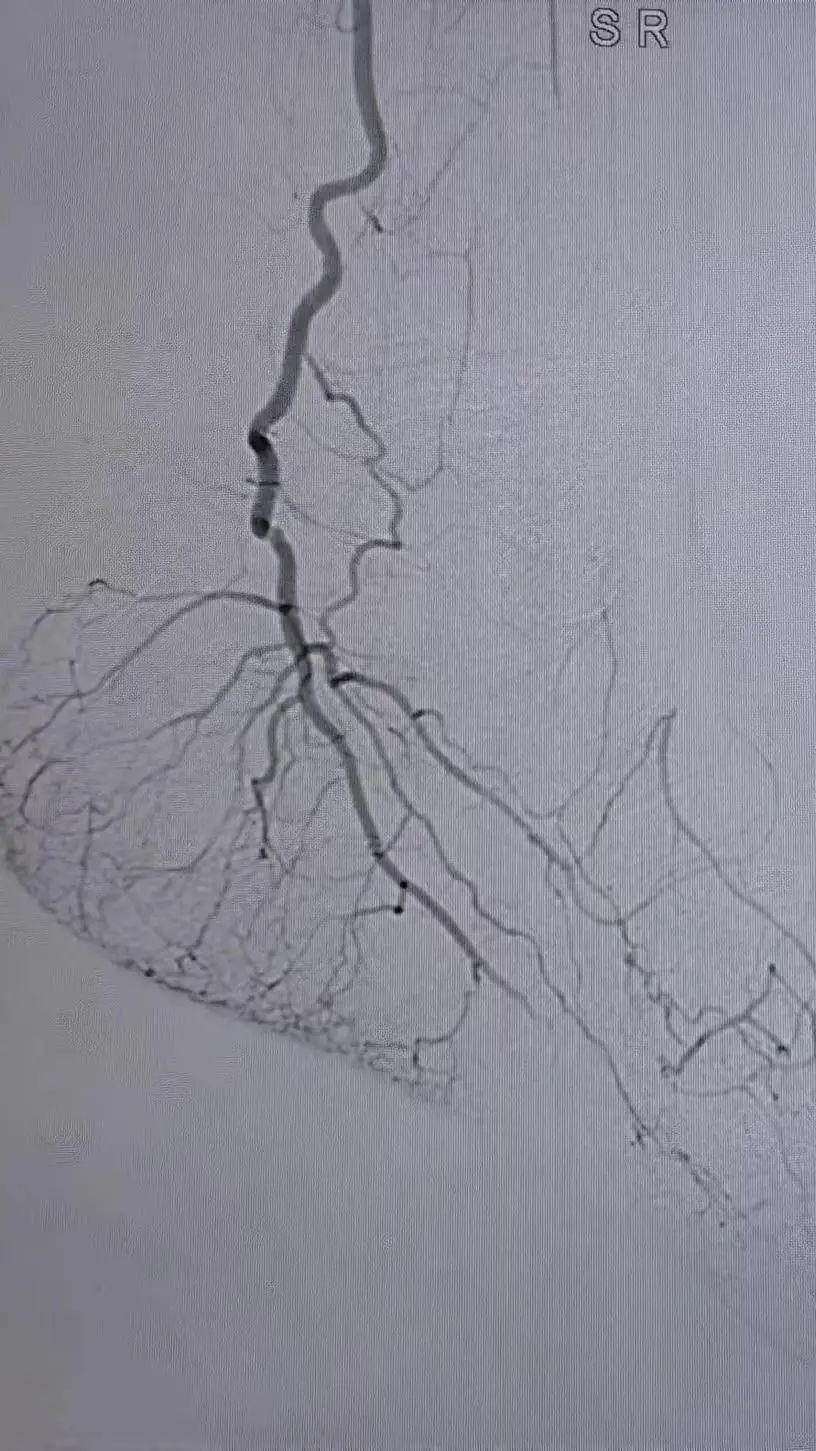

1.穿刺右侧股总动脉,“翻山”至对侧股总动脉,造影:股浅、股深动脉、腘动脉完全闭塞,膝下可见少量侧支动脉代偿。

▲患者术中即时造影显示股浅、股深动脉完全栓塞